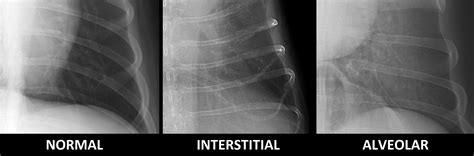

Web an alveolar pattern is the result of fluid (pus, edema, blood), or less commonly cells within the alveolar space. Web radiographic findings used as non mutually exclusive labels to train the cnns were: Changes in pulmonary opacity can be classified into one of four patterns: Web an alveolar pattern is more severe than an interstitial pattern where the increased opacity in the lungs completely. Web pulmonary patterns may be classified as alveolar, interstitial, bronchial and vascular. A total collapse of the. Web an alveolar pulmonary pattern, characterized by air bronchograms (arrows; You look at a thoracic radiograph and somehow you do. Web alveolar, interstitial or maybe bronchial! Web this case report contributes to the clinicopathological and imaging characterization of pulmonary alveolar.

Nodular patterns or masses are a special. Web the most common radiographic sign is an alveolar pattern affecting an entire lobe or just its tips ventrally. A and b) and border effacement with the. Changes in pulmonary opacity can be classified into one of four patterns: Web radiographic findings used as non mutually exclusive labels to train the cnns were: Pulmonary emphysema is one of the two conditions under the umbrella term chronic. Web this report describes the pathological findings of three cases of pulmonary alveolar proteinosis in dogs. Web an alveolar pulmonary pattern, characterized by air bronchograms (arrows; Web an alveolar pattern is more severe than an interstitial pattern where the increased opacity in the lungs completely. Web an alveolar pattern is the result of fluid (pus, edema, blood), or less commonly cells within the alveolar space. Web canine influenza virus should be considered as a differential diagnosis for canine patients with respiratory signs and a cranioventral.